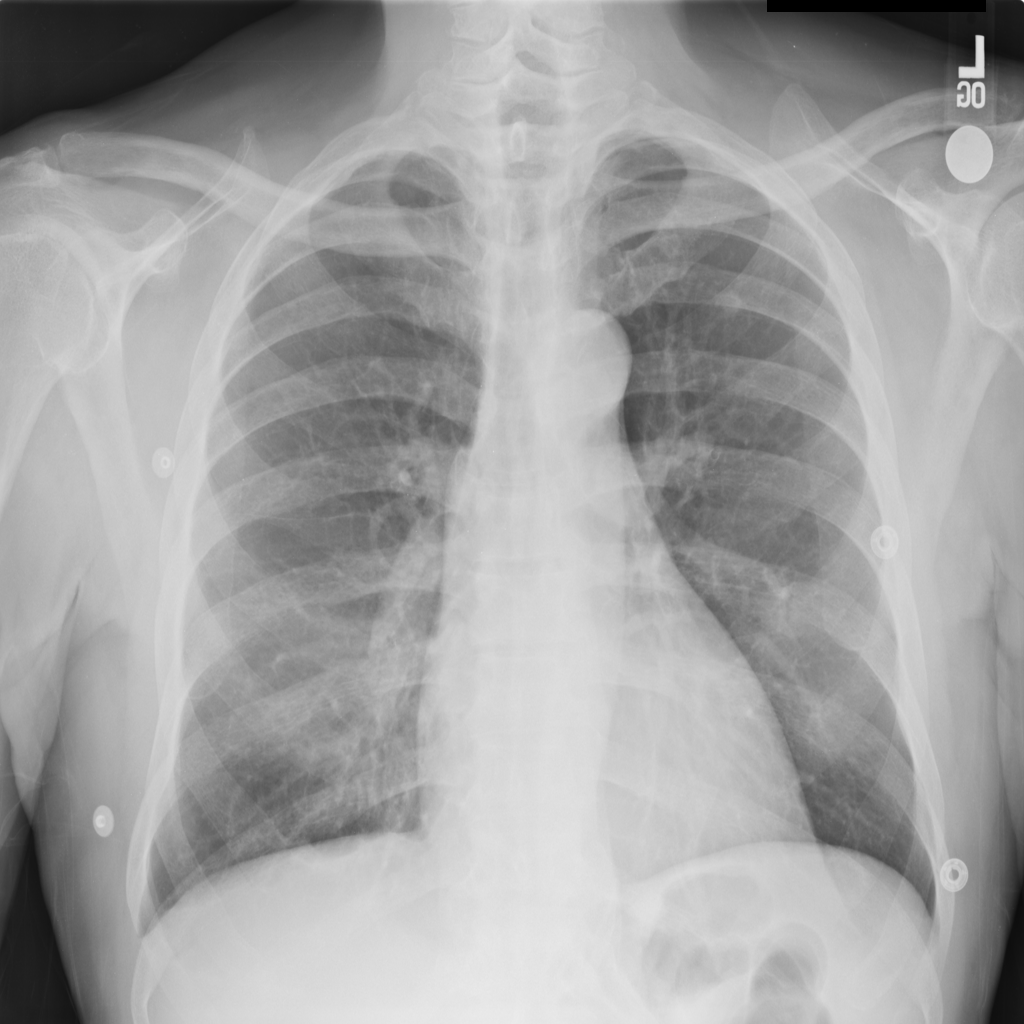

Once the SARS-COV2 reaches the host at the lung, it gets into the cells through a protein called ACE2, which serves as the ”opening” of the cell lock. After the genetic material of the virus has multiplied, the infected cell produces proteins that complement the viral structure to produce new viruses. Then, the virus destroys the infected cell, leave it and infect new cells. The destroyed cells produce radiological lesions [5, 6, 7] such as consolidations and nodules in the lungs, that are observable in the form of ground-glass opacity regions in the XR images (Fig. 1c). These lesions are more noticeable in patients assessed or more days after the onset of the disease, and especially in those older than [8]. Findings also suggest that patients recovered from COVID-19 have developed pulmonary fibrosis [9], in which the connective tissue of the lung gets inflamed. This leads to a pathological proliferation of the connective tissue between the alveoli and the surrounding blood vessels. Given the aforementioned, radiological imaging techniques –using plain chest X-Ray (XR) and/or thorax Computer Tomography (CT)– have become crucial diagnosis and evaluation tools to identify and assess the severity of the infection.

The areas of significant interest used by the CNN for discrimination purposes are identified using a qualitative analysis based on a Gradient-weighted Class Activation Mapping (Grad-CAM) [38]. This is an explainability method that serves to provide insights about the manners on how deep neural networks learn, pointing to the most significant areas of interest for decision-making purposes. The method uses the gradients of any target class to flow until the final convolutional layer, and to produce a coarse localization map which highlights the most important regions in the image identifying the class. The result of this method is a heat map like those presented in Fig. 1, in which the colour encodes the importance of each pixel in differentiating among classes.

The regions of interest identified by the network, were analyzed qualitatively using Grad-CAM activation maps [38]. Results shown by the activation maps, permit the identification of the most significant areas in the image, highlighting the zones of interest that the network is using to discriminate. In this regard, Fig. 1, presents examples of the Grad-CAM of a control, a pneumonia, and a COVID-19 patient, for each of the three experiments considered in the paper. It is important to note that the activation maps are providing overall information about the behaviour of the network, pointing to the most significant areas of interest, but the whole image is supposed to be contributing to the classification process to a certain extent.

The second row in Fig. 1 shows several prototipical results applying the Grad-CAM techniques to experiment 1. The examples show the areas of significant interest for a control, pneumonia and COVID-19 patient. The results suggest that the detection of pneumonia or COVID-19 is often carried out based on information that is outside the expected area of interest, i.e. the lung area. In the examples provided, the network focuses on the corners of the XR image or in areas around the diaphragm. In part, this is likely due to the metadata which is frequently stamped on the corners of the XR images. The Grad-CAM plots corresponding to the experiment 2 (third row of Fig 1), indicates that the model still points towards areas which are different to the lungs, but to a lesser extent. Finally, the Grad-CAM of experiment 3 (fourth row of Fig 1) presents the areas of interest where the segmentation procedure is carried out. In this case, the network is forced to look at the lungs, and therefore this scenario is supposed to be more realistic and more prone to generalizing as artifacts that might bias the results are somehow discarded.

This study evaluates a deep learning model for the detection of COVID-19 from RX images. The paper provides additional evidence to the state of the art, supporting the potentiality of deep learning techniques to accurately categorize XR images corresponding to control, pneumonia, and COVID-19 patients (Fig. 1). These three classes were chosen under the assumption that they can support clinicians on making better decisions, establishing potential differential strategies to handle patients depending on their cause of infection [17]. However, the main goal of the paper was not to demonstrate the suitability of the deep learning for categorizing XR images, but to make a thoughtful evaluation of the results and of different preprocessing approaches, searching for better explainability and/or interpretability of the results, while providing evidence of potential effects that might bias results.

We stand on the fact that automatic diagnosis is much more than a classification exercise, meaning that many factors have to be had in mind to bring these techniques to the clinical practice. To this respect, there is a classic assumption in the literature that the associated heat maps –calculated with techniques such as Grad-CAM– provide a clinical interpretation of the results, which is unclear in practice. In light of the results shown in the heat maps depicted in Fig. 1, we show that experiment 1 must be carefully interpreted. Despite the high-performance metrics obtained in experiment 1, the significant areas identified by the network are pointing towards certain areas with no clear interest for the diagnosis, such as corners of the images, the sternum, clavicles, etc. From a clinical point of view, this is clearly biasing the results. It means that other approaches are necessary to force the network to focus on the lungs area. To this respect, we have developed and compared the results with two preprocessing approaches based on cropping the images and segmenting the lungs area (experiment 2 and experiment 3). Again, given the heat maps corresponding to experiment 2, we also see similar explainability problems to those enumerated for experiment 1. Reducing the area of interest to that proposed in experiment 2 significantly decreases the performance of the system due to the removal of the metadata that usually appear in the top left and/or right corner, and to the removal of areas which are of interest to categorize the images but have no interest from the diagnosis point of view. However, while comparing experiment 2 and 3, performance results improve in the third approach, which focuses on the same region of interest but with a mask that forces the network to see only the lungs. Thus, results obtained in experiments 2 and 3 suggest that eliminating the needless features extracted from the background or non-related regions improves the results. Besides, the third approach (experiment 3), provides more explainable and interpretative results, with the network focusing its attention only in the area of interest for the disease. The gain in explainability of the last method is still at the cost of a lower accuracy with respect to experiment 1, but the improvement in explainability and interpretability are considered critical to translate these techniques to the clinical setting. Despite the decrease in performance, the proposed method in experiment 3 has provided promising results, with an Acc of , BAcc of , GMR of and AUC of .

The COVID-Net has also demonstrated being a good starting point for the characterization of the disease. Indeed, the outcomes of the paper suggest the possibility to automatically identifying the lung lesions associated with a COVID-19 infection (see Fig.1) by analyzing the Grad-CAM mappings of experiment 3, providing an explainable justification about the way the network works. However, the interpretation of the heat maps obtained for the control class must be carried out carefully. Whereas the areas of significant interest for pneumonia and COVID-19 classes are supposed to point to potential lesions (i.e. with higher density and/or with different textures in contrast to controls), the areas of significant interest for the classification in the control group are supposed to correspond to a sort of complement, potentially highlighting less dense areas. Thus, not meaning the presence of any kind of lesion in the lungs.